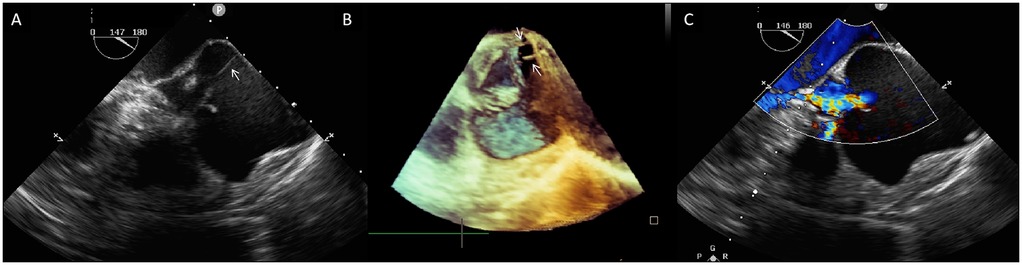

Preoperatively, the patient underwent cardiac CT angiography for procedural planning and risk assessment, which demonstrated the small caliber of the bilateral femoral arteries; thus, transapical TAVR with the J-valve system (Genesis MedTech, China) was planned. Prosthetic size was determined by CT; however, cardiac CT failed to delineate detailed aortic root structures due to significant artifacts. Preoperative transesophageal echocardiography (TEE) was subsequently performed to characterize aortic root anatomy. Confirming TTE findings of the aortic root and cusps, TEE and 3D-TEE additionally identified two ACTs connecting the free margin of the non-coronary cusp to the aortic sinus wall (Figures 1A,B; Supplementary Videos S1, S2). Detailed assessment confirmed that AR was secondary to aortic sinus dilation, with no evidence of cusp restriction or excessive motion (Figure 1C, Supplementary Video S3). This assessment confirms aortic sinus dilation as the primary driver of AR, with ACTs not impacting native cusp motion.

Figure 1. (A) Two-dimensional transesophageal echocardiography (TEE) shows a fibrous strand (arrow) extending from the aortic sinus wall to the free rim of the non-coronary aortic cusp. (B) Three-dimensional TEE shows two aortic chordae tendineae (white arrows)attaching the non-coronary cusp to the aortic sinus wall. (C) Color Doppler TEE demonstrates severe central aortic regurgitation (vena contracta: 7 mm).

This finding raised concerns that ACTs might compromise prosthetic valve stability or cause dislodgment during TAVR. However, anatomical assessment revealed ACTs were eccentrically positioned in the aortic sinus (deviating from the central axis), whereas graspers are deployed centrally in the sinus during TAVR. Thus, TAVR remained feasible, with precise intraoperative grasper positioning enabling ACTs avoidance.